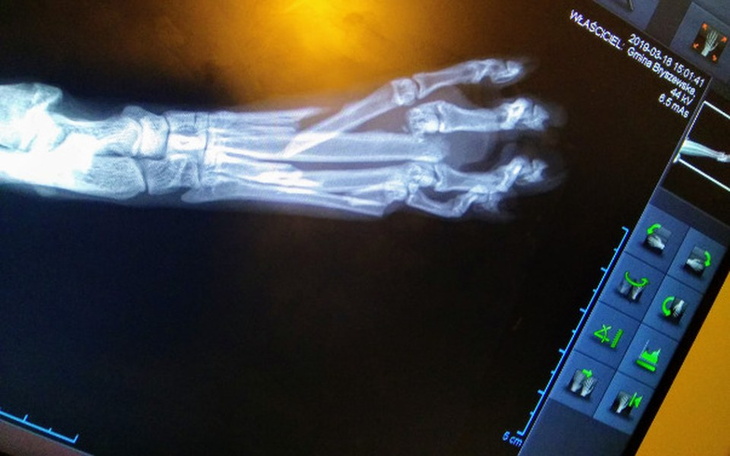

Jeszcze tego samego dnia, w sobotę ma zrobione w lecznicy zdjęcie łapki. Szok :( tego się nie spodziewałam... Owszem, była informacja, że Kocie zostało uderzone a ten incydent miał miejsce 2 tygodnie temu....

Dzwonię do Reni i opowiadam co jest. Mówię, że szukam mu domu, jest taki uroczy, spokojny, ufny i mimo bólu oraz dyskomfortu taki wdzięczny. A do tego jeszcze czeka go operacja...... Drutowanie, gwoździe ....? Nie wiem :( Kocurek ma ok 8 miesięcy. Renia mnie wspiera i zgadza się ze mną. Tak, pomożemy mu.